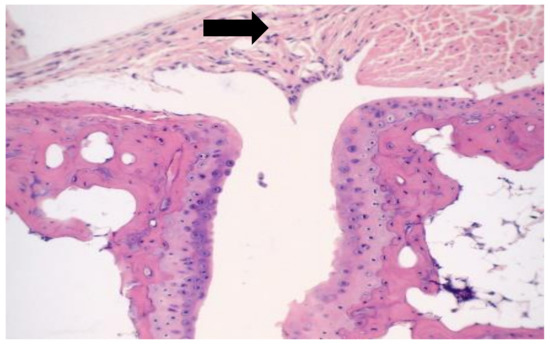

Question : Label the photomicrograph of thin skin. Dermis Duct of ... Expert Answer. 100% (35 ratings) A …. View the full answer. Transcribed image text: Label the photomicrograph of thin skin. Dermis Duct of sebaceous gland Hair Follicle Sebaceous gland Hair Epidermis. Previous question Next question. (Get Answer) - Label The Photomicrograph Of Thick Skin. Stratum ... A) stratum corneum, stratum spinosum, stratum lucidum, stratum granulosum, stratum basale B) stratum basale,... Posted 4 months ago. Q: Procedure Microscopy of Thick Skin obtain a prepared slide of thick skin (which may be labeled "Palmar Skin"), and examine it with the naked eye to get oriented. Once you are oriented, place the slide on the ... Label The Photomicrograph - Mr. Hill's Biology Blog: Our cells "inner skin" Label the photomicrograph of thick skin. Monocyte, erythrocyte, lymphocyte, neutrophil, basophil, eosinophil. (b) for this portion of the problem, we are asked to determine how much total ferrite and cementite form. Photomicrograph is equal to its volume fraction; Label the photomicrograph of thin skin. Layers of the Skin | Anatomy and Physiology I - Lumen Learning Skin that has four layers of cells is referred to as "thin skin.". From deep to superficial, these layers are the stratum basale, stratum spinosum, stratum granulosum, and stratum corneum. Most of the skin can be classified as thin skin. "Thick skin" is found only on the palms of the hands and the soles of the feet.

Anatomy and Physiology Homework Chapter 6 Flashcards | Quizlet Label the photomicrograph of thin skin.-Epidermis-Stratum spinosum-Stratum basale-Stratum granulosum-Stratum corneum-Dermis

The differences between thick and thin skin - University of Leeds Dermis: Thick skin has a thinner dermis than thin skin, and does not contain hairs, sebaceous glands, or apocrine sweat glands. Thick skin is only found in areas where there is a lot of abrasion - fingertips, palms and the soles of your feet. show labels. This is a picture of an H&E stained section of the epidermis of thin skin.

Hair shaft Dermal papillae Epidermis Subpapillary vascular ...